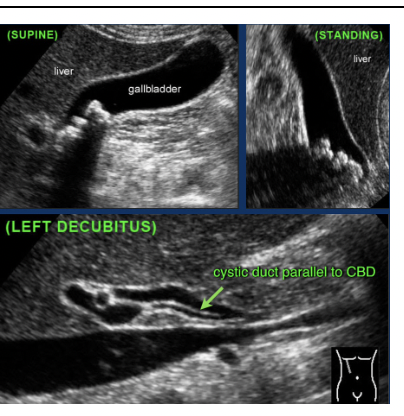

What pathology is in the image below

Sludge - Low level interal echoes, without shadows, no wall/ border